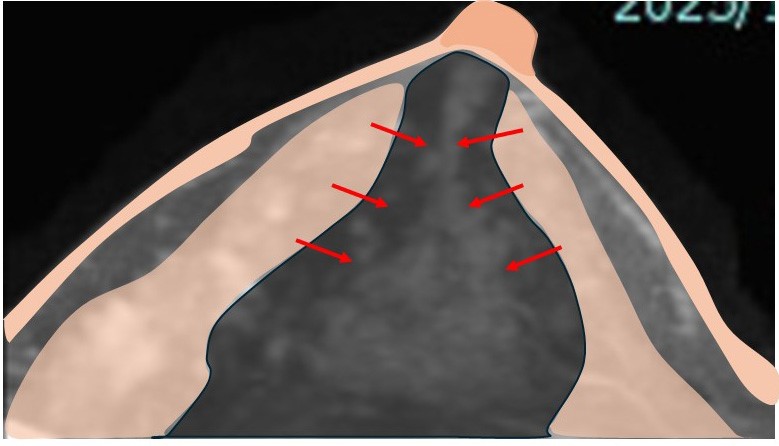

6. 乳腺の(欠損部の)縫合

乳腺の端と端を縫合します。

7. 乳腺の縫合閉鎖

結構大きい欠損なのに、乳腺がそんなに(縫合できるほど)伸びるのか??

8. それには訳があります。

乳腺は「厚み」があるので、それを「薄く引き伸ばす」イメージです。